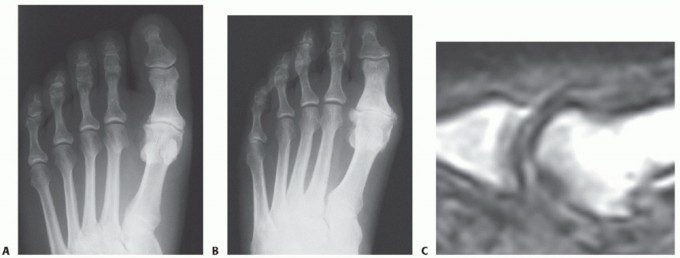

DEFINITION Turf toe injuries involve the capsular-ligamentous-sesamoid complex of the hallux metatarsophalang…